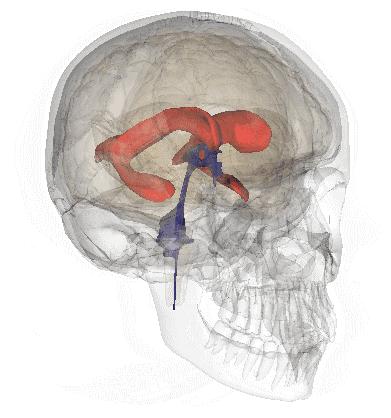

脑室系统

大脑供血动脉3D扫描CT成像

脑脊液循环